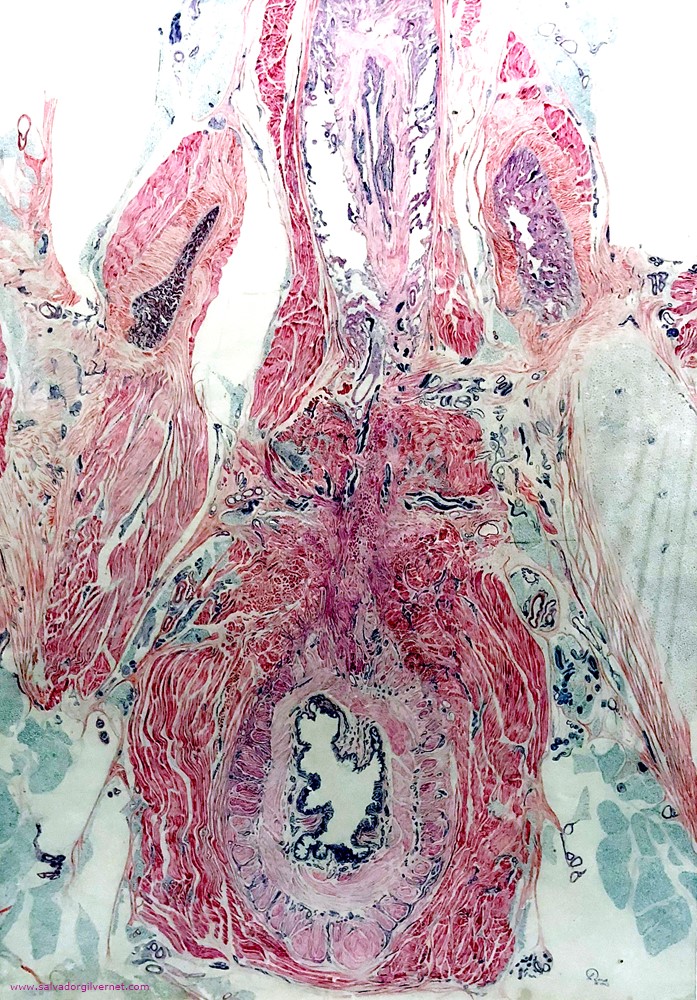

Periné

• Corte histotopográfico transversal

Varón recién nacido

Tinción tricrómica

• L. Roca.  ca. 1948

• Tinta china sobre papel.  81 x 58 cm.

Ramas isquiopúbicas. Cuerpos cavernosos. Uretra bulbar y membranosa. Esfínter uretral externo. Nervios cavernosos y hemorroidales. Músculos bulboesponjoso e isquiocavernoso. Canal anal. Esfínter anal externo.